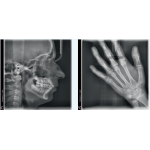

▪ Lateral cabeza L

▪ Mano